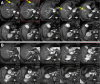

FIGURE 4.

Volume-rendered images of 68Ga-DOTATATE PET/CT scans from first 10 subjects enrolled in cohort 4 (MAD4) before treatment (left side of each panel) and after treatment (right side of each panel) with 4 cycles of 212Pb-DOTAMTATE at dose of 2.50 MBq/kg (67.6 µCi/kg) for each cycle.